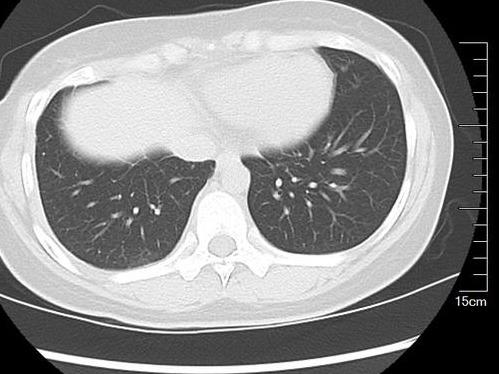

术前CT肺窗显示左侧胸腔积液,双肺血行播散性肺结核